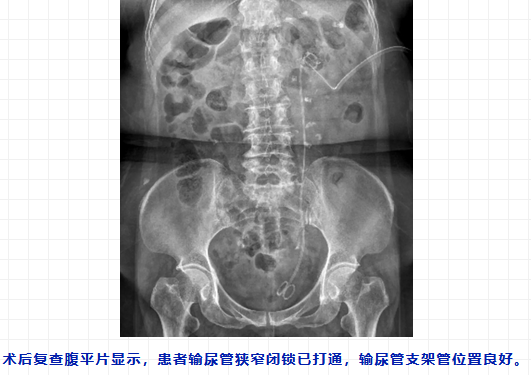

术中,翟建坡主任团队先进行肾镜检查,见肾盂输尿管连接部处闭锁,只能探查其他通路。经细心寻找,医生发现了一条如同针眼大小的通道,仅导丝能穿过,于是进行输尿管镜检查。检查证实导丝可通过输尿管狭窄段,进入膀胱。随后,翟建坡主任沿着导丝置入输尿管球囊扩张器,在输尿管镜监视下将输尿管狭窄段扩张,最后在输尿管内置入两根双J管以防止其再狭窄。手术一气呵成,顺利完成。

术后第2天,李阿姨脱离肾造瘘管,肾功能也在逐步恢复。这场历经3个月的“肾脏保卫战”最终取得胜利。